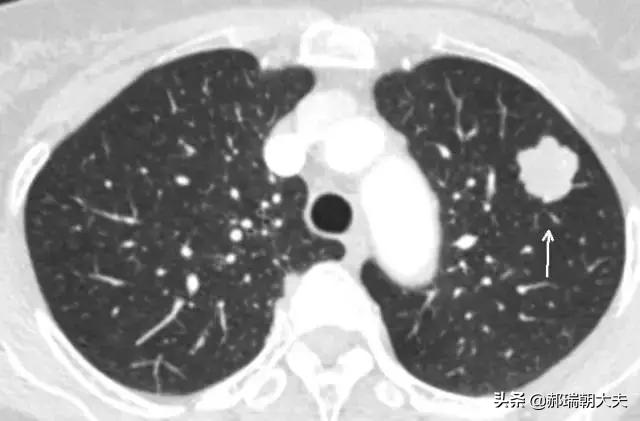

Les examens médicaux étant de plus en plus fréquents, les nodules pulmonaires sont de plus en plus souvent détectés. Les nodules pulmonaires sont un terme d'imagerie, et la définition d'imagerie d'un nodule pulmonaire est une petite lésion bien définie qui est complètement entourée par le parenchyme pulmonaire (Diamètre ≤30mm). La morphologie des nodules est classée comme solide ou sub-solide ; les nodules sub-solides sont eux-mêmes classés en nodules de verre dépoli et en nodules partiellement solides. Les lésions de plus de 30 mm de diamètre sont des masses plutôt que des nodules et ont une probabilité plus élevée d'être malignes.

Des études ont montré que le diamètre du nodule est un facteur prédictif indépendant de la malignité. Plus le diamètre du nodule est important, plus le risque de malignité est élevé, avec les probabilités suivantes : diamètre du nodule <5 mm : <1%;结节直径为5-9mm:2%-6%;结节直径为8-20mm:18%;结节直径>20 mm : >50%.